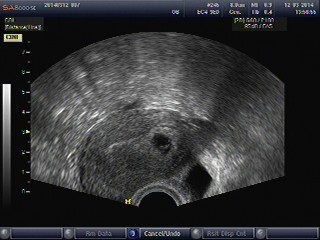

Holky, já jsem to dneska už nevydržela, byla jsem hrozně v nervech, tak jsem se v jednu rozhodla, že k té dr. skočím už dnes. Ordinovala do dvou. A mám dobré zprávy!!

Gestační váček se zvětšil, je v něm žloutkový váček i plůdek o velikosti 4mm a má i srdeční akci! 🙂 ♥♥♥

Podle UZ 6+1tt (dle MS 6+0tt), takže zatím jako z učebnice. Samozřejmě se mi ulevilo a jsem moc šťastná. Takto daleko jsem se ještě nikdy nedostala. Pro můj klid můžu na další kontrolu zase za týden, takže 19.3.

Přikládám i fotečky, moc dobře to vidět nejde (dr. nemá tiskárnu, ukládá to elektronicky a je to jen takhle malé), ale i tak je to krásné.